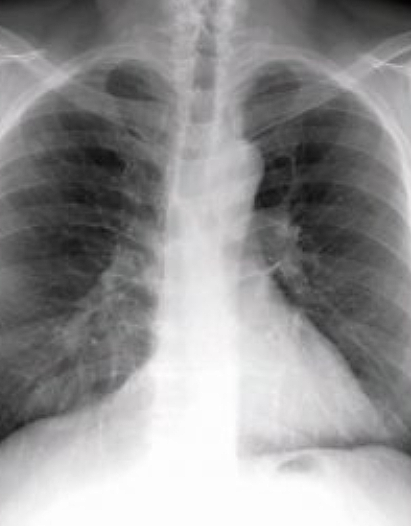

폐 건강 왜 중요한가?

폐와 기도 질환은 사람의 생명과 직결되는 호흡을 담당하고 있어 우리 인체에 가장 주요한 기관이기도 하지만 만성적인 질병으로 이어질수도 있어 무엇보다 예방이 중요합니다.